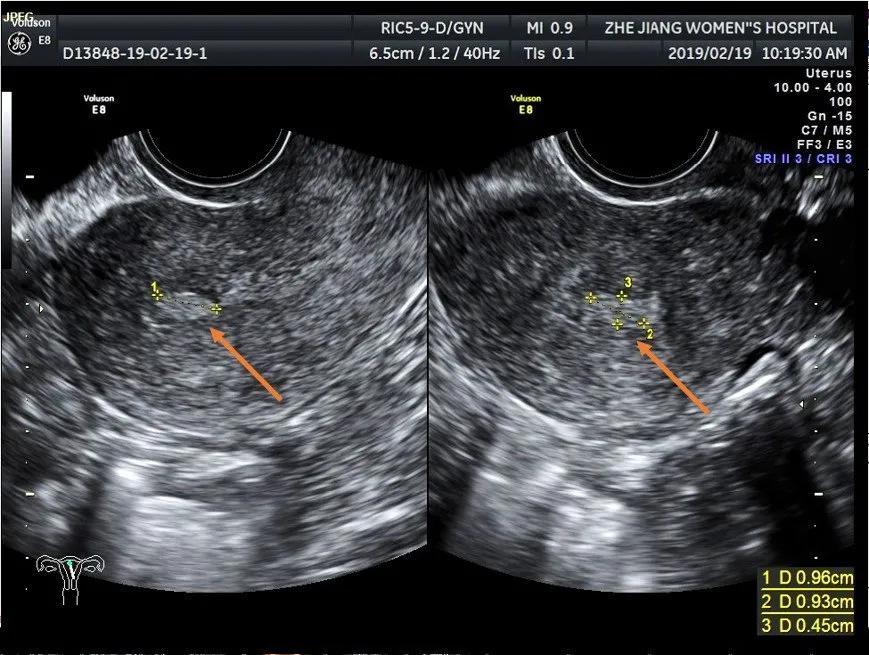

子宫息肉成中-高回声结构,可单个也可多个。

子宫内膜息肉导致宫腔线消失或变形,宫腔内见中-高回声结构,可单发或多个,大小差别很大,常成蛇形,带形或椭圆形。基底部子宫内膜连续可与黏膜下子宫肌瘤鉴别。结节边界清晰,可位于颈管内或宫颈外口。息肉较大时,内膜线显示不清。与子宫内膜癌不易鉴别。 彩色血流显示:中等高阻力的动脉血流或低速的静脉血流信 。 4.子宫内膜息肉病情需要日常监测哪些指标?

标记处息肉